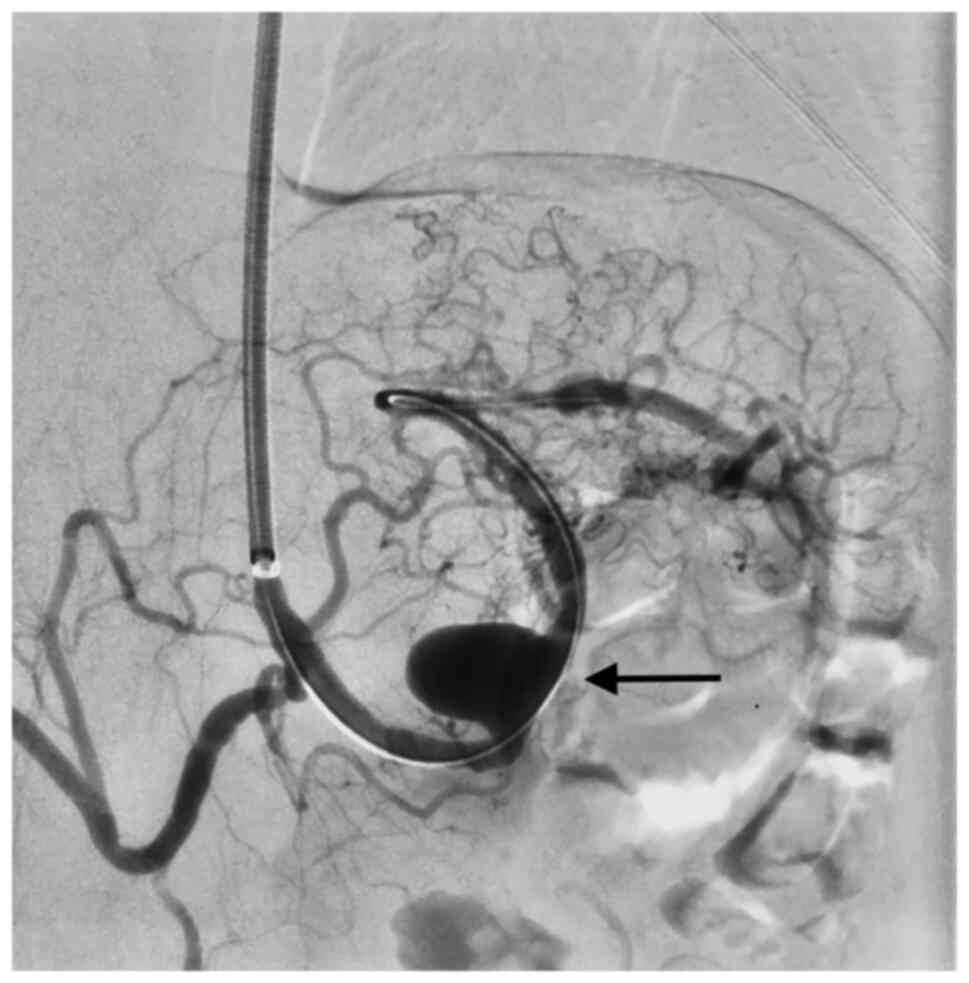

Anastomotic pseudoaneurysms and aortic aneurysms involving the visceral arteries were excluded. The decision to perform an open or endovascular repair was made after discussion in a multidisciplinary meeting (angiology, radiology and vascular surgery). All ruptured VAAs underwent intervention. Open repair was performed in general anesthesia as an aneurysmorrhaphy with or without vascular reconstruction by (direct end-to- end anastomosis or using a vein graft interposition). Endovascular treatment was performed in local anesthesia and consisted either of coilembolization or covered stent placement. If a stent graft placement was technically possible it was performed in order to maintain the vessel patency. If not, a coilembolization was performed.

Six aneurysms of SA, one aneurysm of the CT and one aneurysm of the HA were treated with ER (eight patients). Seven patients were treated with covered stents and one with coiling embolization. In total eight covered stents were implanted. Two patients with SA aneurysms and two patients with SMA aneurysms underwent OS. No allogeneic grafts were required. Three patients needed direct suture only and one a vein graft.

There was no in-hospital mortality and no major postoperative complications (Clavien-Dindo grade ≥3). Technical success was achieved in all patients. The median postoperative stay was four days for all procedures and significantly longer after OS when compared with ER (seven days vs. three days).

In our small patient collective, no mortality was observed. This may be due to the almost total absence of emergency repairs. Considerable mortality is described in the treatment of these patients in an emergency setting (19). In a retrospective study reporting on 185 aneurysms, 46% of the patients were symptomatic with bleeding or rupture. Despite 98% technical success on treating symptomatic patients, 30-day overall and aneurysm-related mortality was 6.2 and 3.4%, respectively. On the other hand, no deaths were observed in patients undergoing elective treatment (20). In another report of 217 splenic artery aneurysms, operative mortality was 5% in the elective group and 20% in the emergency group (8). In another study an operative mortality rate of 37.5% for ruptured superior mesenteric artery aneurysms was described. Also in this study, no mortality was observed for elective repair (21). In another large retrospective study, morbidity (19% vs. 4%; P=.003), 30-day mortality (13% vs. 0% P=0.001), 1-year (32.5% vs. 4.1%, P<.001), and 3-year mortality rates (36.4% vs. 8.3%; P<.001) were significantly higher for ruptured aneurysms than for intact aneurysms. Open surgery had higher 30-day mortality rates thanendovascular repair (28% vs. 7%; P= .06) (22). In our retrospective patient cohort, length of stay was shorter in the ER group (mean difference -4.25 days, 95% CI [-5.52; -2.98], P<0.00001; seven vs. four days). Comparable results regarding the length of stay were reported in a previous meta-analysis (23). The technical success of 100% when using endovascular stentgrafts or coiling observed in our patient collective may reflect the bias inherent in the analysis of a very small patient collective. In a systematic review and meta-analysis from 2016 comprising 22 studies reporting on endovascular treatment of VAAs, a 93.2% technical success rate was reported (24).